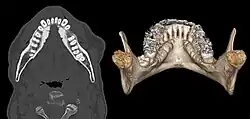

| Mandibular torus in premolar area | |

Torus mandibularis is a bony growth in the mandible along the surface nearest to the tongue. Mandibular tori usually are present near the premolars and above the location on the mandible of the mylohyoid muscle attachment.[1] In 90% of cases, a torus is on both inner sides of the mandible (left and right); however, they may differ in size.